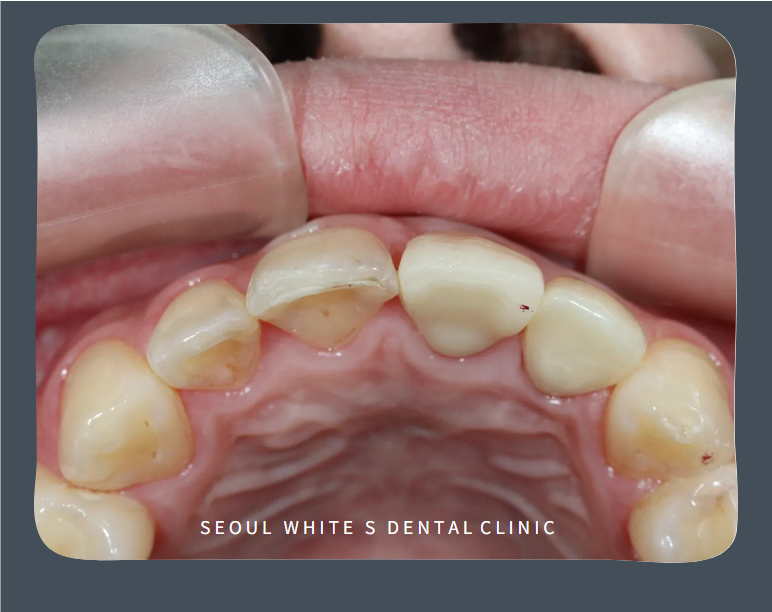

영도구치과추천 서울화이트S치과는 위 앞니 사이 인접면 우식과 깨진 치아로 일상생활에 불편함을 느끼고 계신 분의 심미치료 사례를 소개해 드리겠습니다.

영도구치과추천 서울 화이트S치과에 처음 내원하셨을 때 모습입니다. 오른쪽 큰 앞니와 작은 앞니(사진에서 왼쪽) 인접면 치아우식으로 검게 변색되어 있었으며, 왼쪽 작은 앞니는 깨져있으셨습니다.

치아우식 부위의 정도를 확인한 후 레진을 진행하고 크랙이 생긴 부위는 보철치료를 진행하기로 계획을 수립하였습니다.